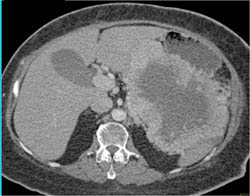

Antral Carcinoma